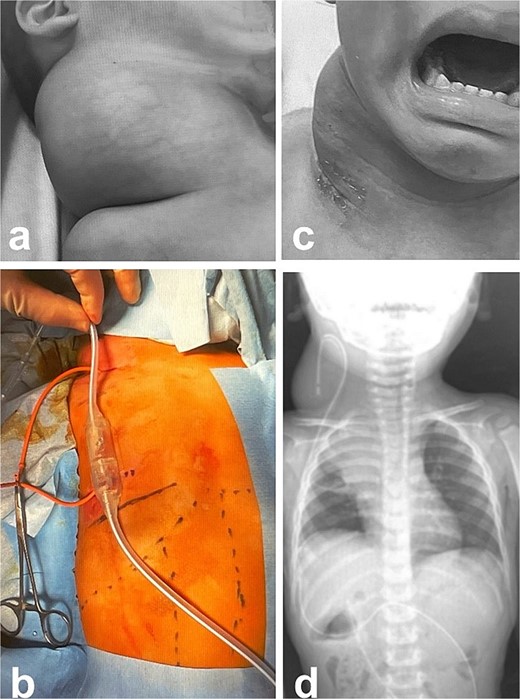

Intra- and post-operative findings from the second operation. (a) The X-ray showed that the tip of the catheter may have moved within the cyst, causing the catheter tip to penetrate the cyst. (b) The X-ray showed the rounded tip of the catheter fixed with threads. (c) Intraoperative findings showed that the tip of the catheter penetrated the cyst wall (black arrow). (d) There were cyst walls with a septum on the mediastinal side of the cyst and when incised old bleeding was noted. The walls were opened as much as possible. (e) The tip of the catheter was rounded and fixed with threads. The catheter was then placed back into the cyst and the wound was closed.

A male infant weighing 2726 g was born at 38 weeks of gestation. Antepartum ultrasonography and magnetic resonance imaging (MRI) revealed a right cervical cyst, suggestive of a lymphangioma. A right cervical cyst was noted at birth and gradually decreased in size thereafter. However, right cervical swelling became evident when he cried (Fig. 1a and b). An MRI obtained at 21 months of age showed a huge cyst in the right cervical mediastinal region. Following diagnosis of a lymphangioma with hemorrhage, he was treated with Eppikajutsuto®, a Japanese traditional Kampo medication, 2 g/d (0.2 g/kg). An MRI revealed tumor enlargement after oral administration of Eppikajutsuto® for 2 months. A complex vascular malformation was noted (Fig. 2) and the dose was increased to 5 g/day (0.5 g/kg). A repeat MRI 2 months after the dose increase showed no reduction in the size of the tumor. After another 4 months, the dose of Eppikajutsuto® was further increased to 7.5 g/d (0.65 g/kg). The tumor in the cervical region had enlarged further with an accompanying risk of airway system compression (Fig. 3a–c). A puncture and suction of the lymphangioma was performed for volume reduction and the content was prepared for bacterial culture. The content was dark red in color, which was consistent with hemorrhage. The white blood cell count (WBC) was 19 190/μl and the C-reactive protein (CRP) concentration was 5.77 mg/dl. He was admitted to the hospital to undergo treatment with intravenous and oral antibiotics. The bacterial culture results were negative. On the 22nd day of hospitalization, the WBC count was 8780/μl and the CRP concentration was 0.39 mg/dl. On the 24th day of hospitalization, a Denver shunt was inserted from the right cervical region to the abdominal cavity to reduce the volume of the cervical cyst to prevent airway obstruction (Fig. 4a–c). A pump chamber with a backflow prevention valve was implanted in the right anterior chest subcutaneous tissue (Fig. 4b). By applying pressure to the chamber, the cyst fluid in the neck was returned to the abdominal cavity. The patient was discharged on the 6th post-operative day. The swelling in the right neck was reduced and the pressure on the trachea was relieved based on the X-ray findings (Fig. 4c and d). On the 5th day after hospital discharge, the patient was febrile and the right neck swelling recurred. A hemogram revealed severe anemia and bleeding within the neck cyst was suspected. He was readmitted to the hospital and on the 2nd day after admission the cervical cyst was punctured, which yielded bloody contents. A transfusion was performed for anemia secondary to hemorrhage in the neck cyst. Sirolimus (1 mg), a mammalian target of rapamycin inhibitor, was added 7 months after starting Eppikajutsuto® due to a concern that administration of a Kampo medication and insertion of the Denver shunt might not be effective. An X-ray showed that the tip of the catheter may have moved within the cyst, which caused the catheter tip to penetrate the cyst and resulted in bleeding within the neck cyst (Fig. 5a). Serial MRI findings showed that the old bleeding site was within the mediastinal region of the lymphangioma. Revision surgery was performed 3 weeks after inserting the Denver shunt. Intraoperative findings showed that the tip of the catheter had penetrated the cyst wall (Fig. 5c). There were cyst walls with a septum on the mediastinal side of the cyst and when incised old bleeding was noted and the walls were opened as much as possible (Fig. 5d). The tip of the catheter was rounded and fixed with threads. The catheter was returned to the cyst and the wound was closed (Fig. 5b). The patient was discharged 9 days after the 2nd surgery. The concentration of sirolimus on the 14th day of administration was 9.9 ng/mL (normal range: 5–15 ng/ml). On the 16th day after the second hospital discharge, the neck had enlarged, the surgical wound was erythematous, and discharge was noted at the site of the pump chamber. Bacterial cultures of the punctured the neck cyst content and the wound discharge grew Staphylococcus aureus. On the 24th day after the 2nd hospital discharge, the blood concentration of sirolimus 1 month after starting oral administration was 19.7 ng/ml. Therefore, the oral administration of sirolimus was temporarily discontinued. At the same time the patient developed a high fever and the 3rd operation was performed to remove the Denver shunt due to a catheter infection. The blood concentration of sirolimus 6 days after discontinuation was 1.4 ng/ml. An MRI on the 6th post-operative day from the 3rd operation revealed two different intensities in the neck and mediastinal regions where the Denver shunt was inserted (Fig. 6a). On the 10th day after the 3rd operation, the patient was discharged from the hospital but laboratory testing showed an elevated WBC count (13 250/μl) and CRP concentration (6.03 mg/dl). Three months after the 3rd hospital discharge, the right neck swelling abruptly decreased in size and the WBC count and the CRP concentration decreased to the normal range. An MRI 2 months after the 3rd operation showed that the mediastinal lesion was smaller with near-complete regression (Fig. 6b). The neck swelling was minimal 6 months after the 3rd operation. An X-ray showed no tumor shadow and no compression of the trachea by the lymphangioma (Fig. 6c) and magnetic resonance angiography (MRA) showed that the lymphangioma had regressed (Fig. 6d). Currently, no right cervical swelling is evident when the patient cries (Fig. 6e and f) and he is doing well with oral administration of Eppikajutsuto® (7.5 g/d [0.65 g/kg]).